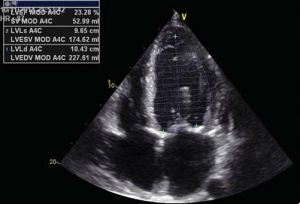

A 56 year-old male patient with obesity (body mass index of 30.1 kg/m2, body surface area of 2.1 m2) and a history of permanent atrial fibrillation on oral anticoagulants, with type II diabetes mellitus on oral antidiabetic drugs and hyperlipidemia was referred to our Center to be assessed for trans-catheter aortic valve replacement (TAVR). He was declined conventional surgical treatment by several cardiac surgical teams because of significant impairment of the LV systolic function. On admission the patient presented with NYHA class III heart failure; he had previous NYHA class IV transient episodes. He never experienced angina or syncope. The ECG demonstrated atrial fibrillation and signs of left ventricular hypertrophy and strain in the left precordial leads. His echocardiogram showed dilated cardiomyopathy (LV end-diastolic volume of 195 ml) with severe impairment of the left ventricular function and an ejection fraction of 20%. His heart failure was due to severe calcified aortic stenosis with an indexed valve area of 0.47 cm2 /m2, and peak/mean gradients of 62/39 mmHg (Figure 1). He also had moderate-to-severe mitral regurgitation and severe tricuspid regurgitation with an estimated sPAP of 38 mmHg. He was considered at high risk for surgery due to the very poor left ventricular performance. Blood samples showed good renal function, moderate liver dysfunction consistent with congestive hepatic disease, long standing uncontrolled diabetes with high glycated hemoglobin (8.2%). NT proBNP level on admission was 10854 pmol/l.

Trans-thoracic and trans-esophageal echocardiography were performed for the analysis of the aortic valve, which proved to be bicuspid, with severe calcifications, associated with a moderately dilated ascending aorta of 38 mm diameter and poor left ventricular ejection fraction (Figure 2). Coronary angiography demonstrated non-significant obstructive coronary artery disease. Multi-slice angio-CT of the entire aorta was performed for the assessment and measurements of the aortic root complex (valve and ascending aorta) and the ilio-femoral axis (Table 1). The aortic valve was confirmed as bicuspid with a raphe between the right and the non-coronary cusp and a single sagittal commissure. The aortic annulus had a minimum diameter of 26.8 mm and a maximum diameter of 31.9 mm, with a perimeter of 93.7 mm; the perimeter derived annulus diameter was 29.8 mm (Figure 3). The distance from the annulus to the ostia of the coronaries allowed the implantation of a balloon expandable valve. Both common external iliac arteries proved to be calcifi ed with an internal diameter less than 6.5 mm prohibiting the femoral approach with the classical 18 French TAVR sheath (Figure 4). Accordingly, the Heart Team decided to proceed with TAVR using the trans-apical approach with a 29 mm Sapien XT trans-catheter heart valve system. The patient and his family were fully informed about procedural steps and about the age limit admitted in the guidelines that he did not fulfill at 56.

Figure 2. Echo measurements of aortic annulus, diameter at Valsalva sinuses and ascending aorta (Figure 2A). LV function – ejection fraction (Figure 2B).

impairment. He was discharged on a regular ward 24 hours after the procedure when the temporary PM lead was also extracted. He remained hemodynamically stable, without inotropic drug support, low IV loop diuretics and no pericardial effusion. Transthoracic echocardiography before discharge showed that the Sapien XT valve had a good stable position, with a minimal para-valvular leak, associated with mild improvement of the left ventricular function, with a 25% ejection fraction. In the 7th day after the procedure and prior to discharge the patient performed a 6 minutes walking test for 260 m without any signifi cant symptoms. He was left on acenocumarol for a target INR between 2.0- 2.5, clopidogrel and low dose aspirin; triple therapy was considered for 6 months and acenocumarol and clopidogrel should be given thereafter. One year after valve implantation he remained in good clinical condition, in NYHA class II with a marked improvement of mitral regurgitation, but with persistent LV systolic dysfunction and a 25% ejection fraction.